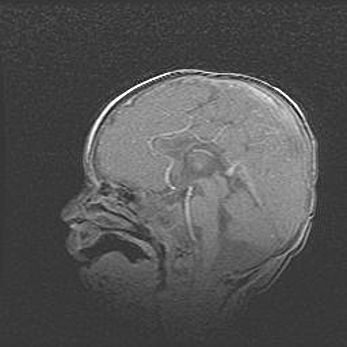

Церебральная ишемия II.

Возраст: 5 дней

Вес: 3400 г

Пол: женский

Окружность головы: 35 см

Срок гестации: 39 недель

Церебральная ишемия – это заболевание, характеризующееся недостаточностью (гипоксией) либо полным прекращением (аноксией) снабжения мозга кислородом по причине закупорки одного или нескольких сосудов. Это приводит к  что метаболическим расстройствам различной степени тяжести в тканях головного мозга, развитию коагуляционных некрозов и гибели нейронов.